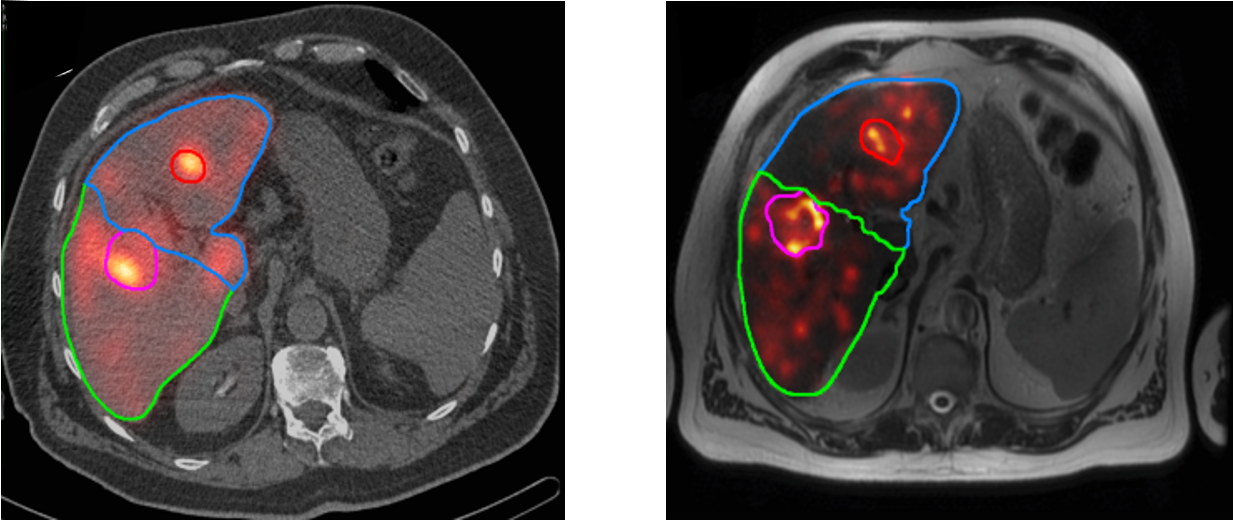

Albumin microaggregates (MAA) are very small particles (a few microns) which tend to accumulate in microvasculature, much like resin or glass microspheres. MAA labeled with 99mTc are used to simulate a SIRT treatment: the 99mTc-MAA is released in selected branch(es) of the portal vein, and the result is imaged with SPECT. SPECT imaging must be done shortly after MAA-administration, because unlike the therapeutic microspheres, MAA is only trapped temporally. The 99mTc-MAA study is done to check if the injected particles will remain in the liver, or if a significant portion of them ends up in the lungs. In some patients this happens, because their vasculature has some liver-to-lung shunts. The study is also done to verify that the catheterization procedure will reach all the tumors. Figure 7 shows transaxial slices from a pre-treatment 99mTc-MAA image and the corresponding post-treatment 90Y-PET image. In this study, a good agreement between the pre- and post-treatment images was obtained.

Figure 7:Left: the 99mTc-MAA image (in color) fused with the corresponding CT image (black and white), from the pre-treatment SPECT/CT image. Right: the 90Y-PET image fused with the corresponding MR image, from the post-treatment PET/MR image.